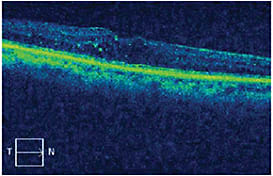

Six weeks after combination therapy, the CFT had decreased to 352 µm and visual acuity had improved to 20/60-2 (Figure 2). The swelling remained stable for 3 months (Figure 3), after which the CFT increased to 546 µm.

Figure 2. Six weeks post combination therapy.